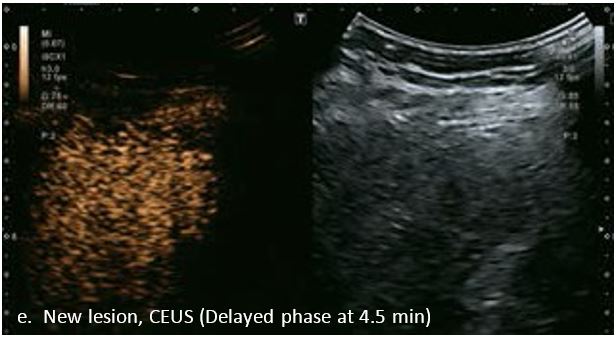

Оцінка результатів лікування ГЦК

Проведено повторне обстеження 79-річного чоловіка з цирозом печінки В, ускладненим ГЦК, після транс-артеріальної хіміоемболізації (ТАХЕ). Було виявлено нове ураження, розташоване поруч з ураженням після ТАХЕ. На сірошкальному зображенні чітко видно нове ураження, але складно виявити рецидив ГЦК в зоні ураження після ТАХЕ. За допомогою кольорового картування SMI (cSMI) можна побачити розвинену судинну мережу всередині нового вогнища ураження. Для оцінки результату лікування було виконано CEUS. За допомогою CEUS можна легко дослідити як нове ураження, так і рецидив ГЦК у вогнищі ураження після TACE. Нове ураження демонструє гіперпосилення артеріальної фази і відсутність вимивання до 5 хвилин, отже, це ураження LI-RADS 4, ймовірна ГЦК за критеріями LI-RADS. Підживлюючі судини можна чітко спостерігати в ранній артеріальній фазі. Для ураження після TACE, більша його частина не підсилюється, однак, в артеріальній фазі спостерігається ділянка гіперпосилення у верхній частині лікованого ураження, що вказує на рецидив ГЦК.

Малюнок 10